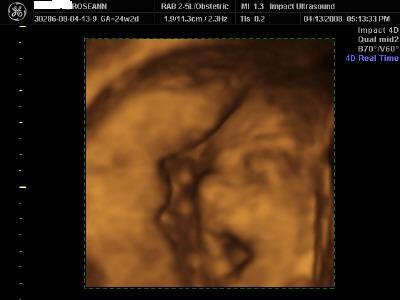

Here are 3D pics of Seamus Finn I was a little over 24 weeks when I had them done yesterday. i went to Impact Technologies in East Meadow. They were great. We bought all the grandparents and they got to sit on couches and they projected the sonogram on a big movie screen on the wall! We went out to dinner afterwards and our parents surprised us and told us they are buying all 4 pieces of our furniture!! We are very excited

The first pic is my absolute favorite. He didnt want to be bothered much. He kept turning his @ss to us and we had to jiggle my belly to get him to flip!! And the tech said that he definately has hair! He showed us in 1 of the pics the squiggly lines! Image Attachment(s):